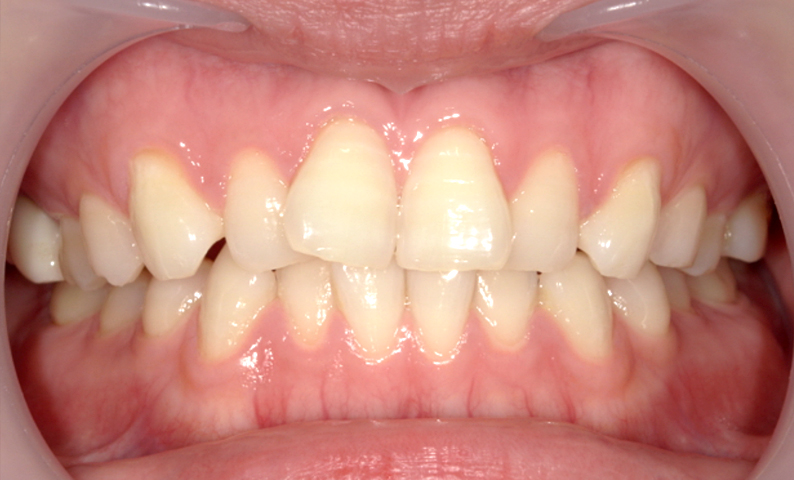

症例_001 前歯「八の字/V字型」症例

治療期間:17ヶ月金額:54万円+税20代女性八の字/V字型

| Before | After |